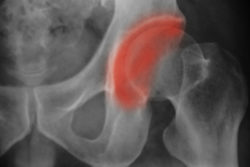

Plaintiff Roy B. claims the metal on metal hip implant components had caused each other to wear down and shed metal debris into his bloodstream, which ultimately resulted in DePuy hip replacement failure. According to the DePuy metal hip lawsuit, Roy had the DePuy ASR hip implant implemented for typical treatment purposes on Nov. 20, 2006.

Roy and other patients allege that DePuy hip replacement failure occurred due to a serious design flaw in their components. More specifically, metal ions and debris can be shed into the bloodstream when the all metal ball and socket joint components interact. This causes blood metal ion levels to rise to dangerous levels, which can cause serious complications like increased risk of cancer and cardiomyopathy.